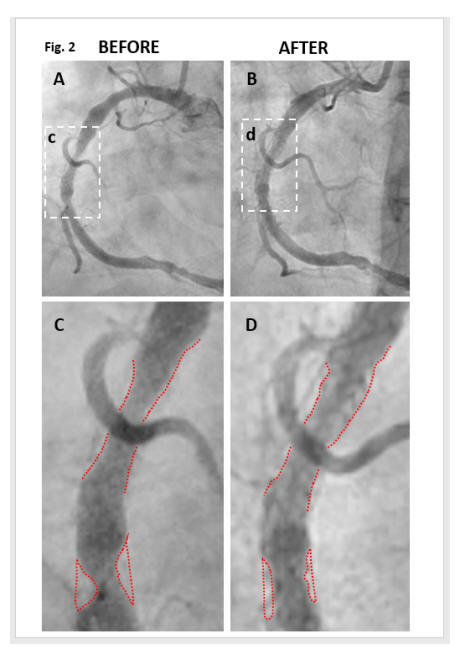

Direct Angiographic Evidence of Coronary Disease Reversal

If you benefit from cyclodextrin, then thank Kyle Hodgetts. Kyle, a hypertensive, hyperlipidemic, long-standing smoker, by age 56, had required several rounds of stent placement. Standard medicine was not working. Kyle's physicians gave him little hope for future health. The adage "Necessity is the Mother of Invention" certainly applied here. Kyle had just lost his wife to illness. The couple had two young children. What would happen to them if Kyle died? Kyle, a researcher, read Dr. Zimmer's article (convincing animal model evidence that cyclodextrin will reverse atherosclerosis). I also read this article too, got excited, and soon after lost interest as cyclodextrin was then not available in the US. Kyle read the Zimmer study, and then every other paper he could find on this molecule (there is a lot - I've now read it all too). Kyle found a source of pharmaceutical grade CD, and then, assisted by his medical and scientific team, began to treat himself with IV cyclodextrin. Kyle and his medical group kept careful records and published the results. As depicted below, Kyle experience rapid (months, not years) coronary disease regression (documented by angiography), corroborated by carotid plaque regression (documented by ultrasound), and his lipid panel improved. Representative images are presented below. You can read the published reports yourself (Kyle's coronary angiogram, Kyle's' carotid ultrasound). Kyle tells his story, and discusses the science of cyclodextrin, on cholrem.com. You will note that everything Kyle says is pretty much everything that I am saying. I am not parroting Kyle, nor visa versa. We both studied the literature and came to the same scientific conclusions. The outcomes experienced by Kyle's clients are just what my patients are experiencing (as presented below). Cyclodextrin, once it is understood by all (a job I have assigned to myself) and put into widespread use, is going to save millions of lives, decrease the need for surgical interventions, and save billions of dollars. Kyle, in this regard, deserves a Noble Prize - he brought this to you!